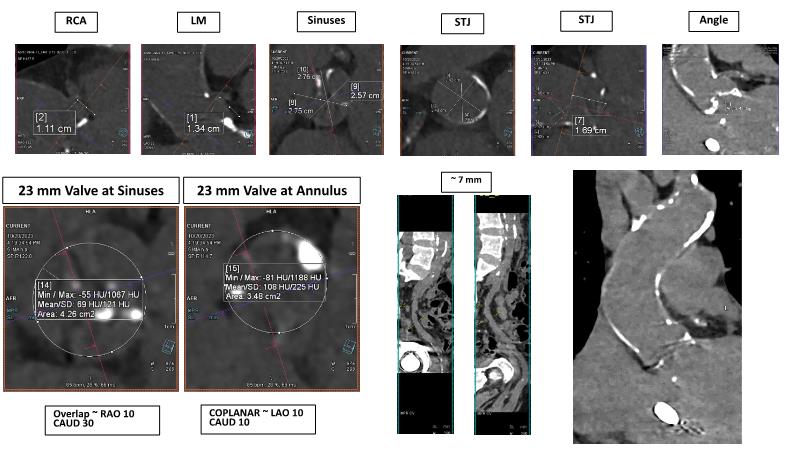

The primary focus of this GulfPCR-GIM 2023 session revolves around pre-procedural planning considerations, valve selection, and managing complex anatomies using both traditional self-expanding valves and the Evolut FX system. Additionally, the session aims to explore the work-up protocol for patients grappling with severe AS and advanced CKD, elucidate the algorithm for selecting the appropriate TAVR platform, discuss strategies to reduce contrast utilization, and highlight the distinctive advantages offered by the Evolut FX system.

• To discuss valve choice in challenging anatomies

• To learn more about optimization of valve deployment